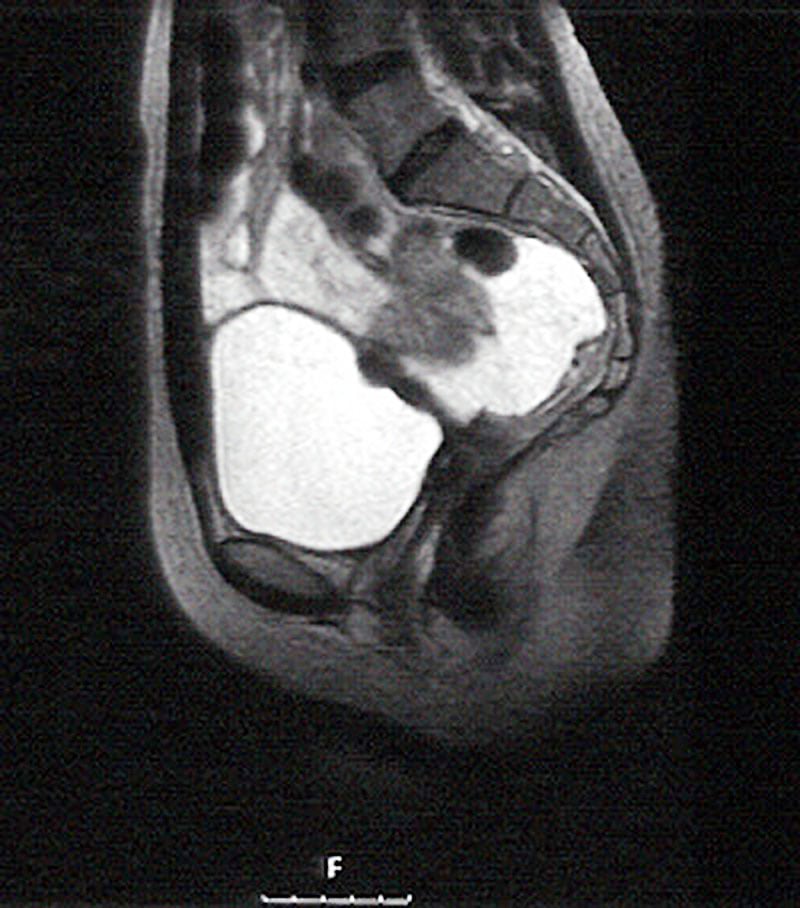

Je nach Symptomen und Fragestellung kann auch eine Untersuchung mit anderen Verfahren sinnvoll sein, z.B. eine Darmspiegelung oder bildgebende Verfahren wie die Kernspintomographie.